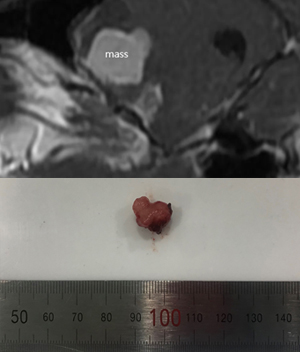

고양이에서 발생하는 뇌종양 중에서 가장 빈발하는 뇌종양이며 주로 대뇌반구 수막 외측에 발생합니다.

개와 달리, 고양이 뇌수막종은 예후가 양호합니다.

뇌종양의 경우, 수술 중 종양에 대한 접근이 까다롭기 때문에 정확한 검사와 진단이 필수입니다.